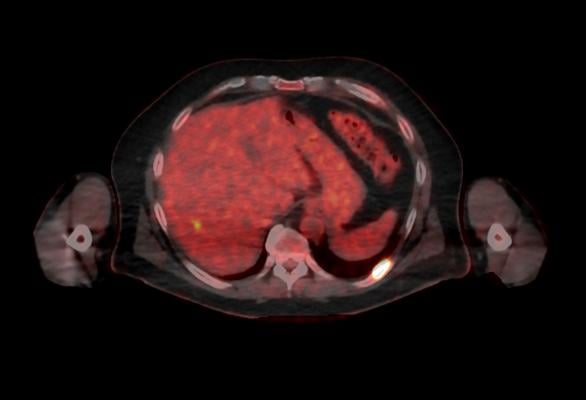

Single photon emission computed tomography (SPECT) is currently the biggest application of gamma cameras given the low cost, large suite of radioisotopes and expanded use cases. According to FMI, however, positron emission tomography (PET) is anticipated to witness the fastest growth in terms of adoption, owing to the greater special resolution and sensitivity brought about by the use of positron emitting radioisotopes that provide more energy, contrast and special resolution.